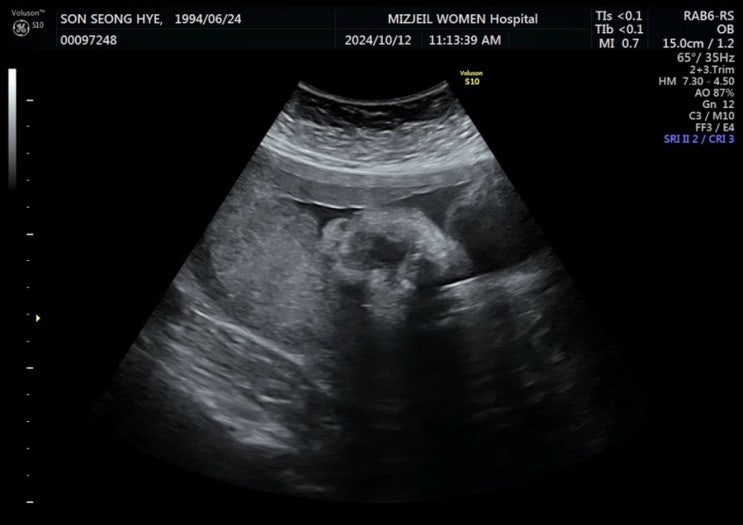

임신 이야기 - 33주 1일, 정기검진 및 이모저모 그리고 출산 전 휴가 시작

24.11.16 33주 정기검진! 지난 검진 때 아기가 좀 커서 식사량을 줄이라고 하셨었다 ㅋㅋ 줄이지 못한 나.....

임신 이야기 - 30주 1일, 정기검진 및 방꾸미기 시작

24.10.26 30주 1일차 28주 검진에서 아기가 아직 돌지 않았다는 소식을 들은 뒤 첫 검진! 가장 궁금했던 아...

임신이야기 - 28주 1일, 정기검진(경부 길이 확인 외) 및 백일해 주사

오늘은 28주 정기검진날 ~ 요즘 자주가는 것 같은 기분은 왜지?!ㅋㅋ 이번 정기검진에서는 몇 가지 궁금한 ...